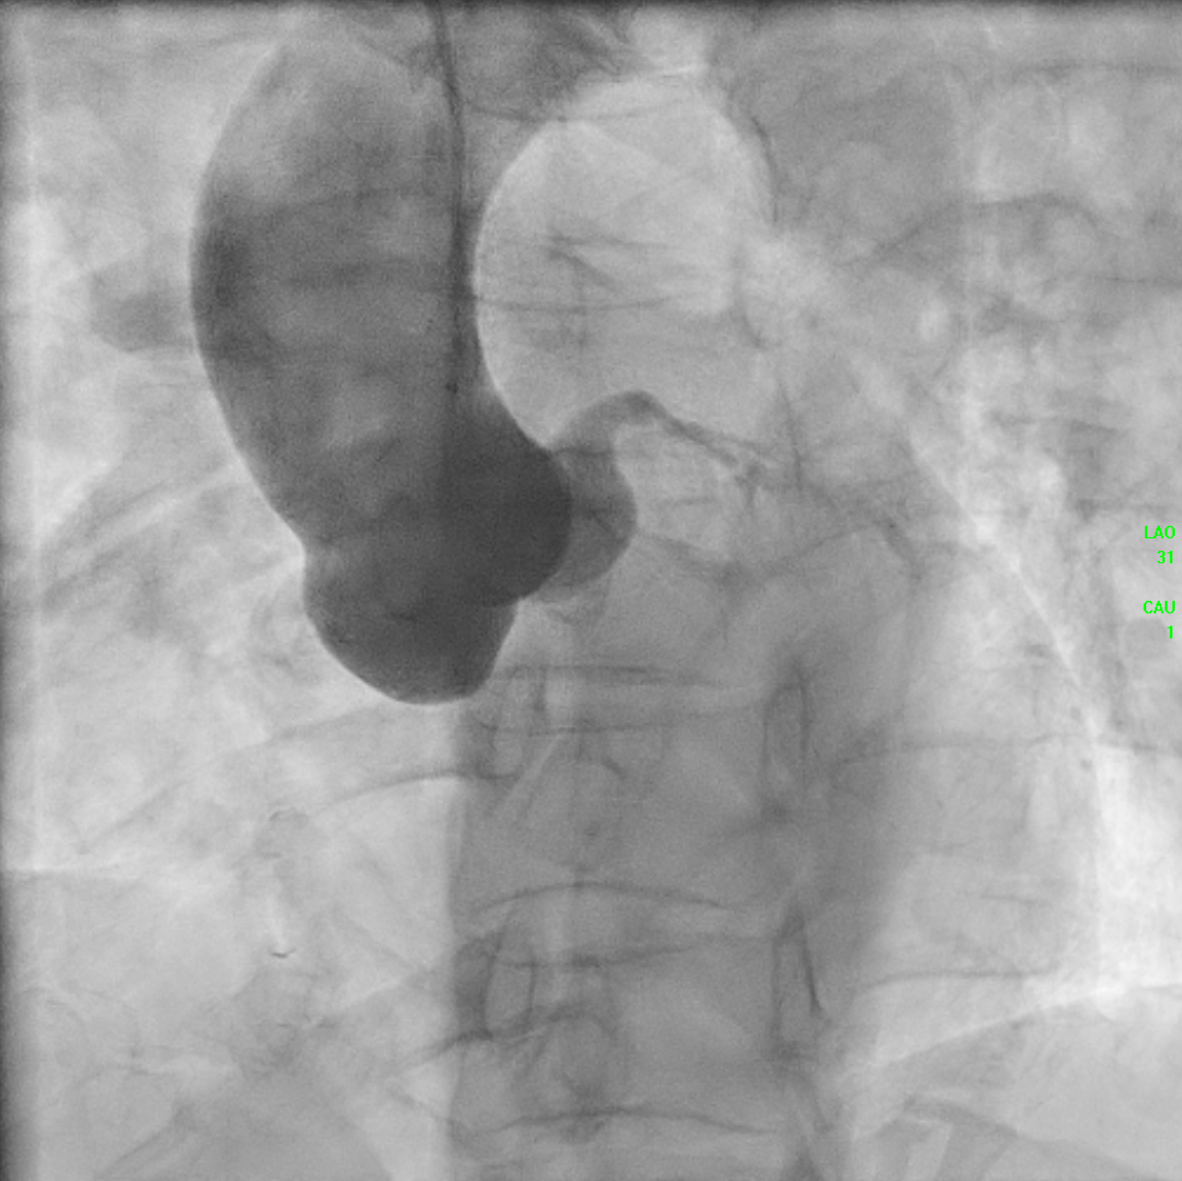

The initial angiogram on July 3rd, 2025, showed two-vessel coronary artery disease, with diffuse atherosclerosis extending from the proximal to distal LAD and moderate stenosis of the OM2. The RCA was absent and appeared to be supplied by the D1 branch, which showed severe disease at the ostium and mid segment. A repeat angiogram showed drop of blood flow with TIMI 2 flow to the distal LAD and RCAterritories. Then we proceed to PCI to LAD and RCA.

AORTOGRAM.mp4